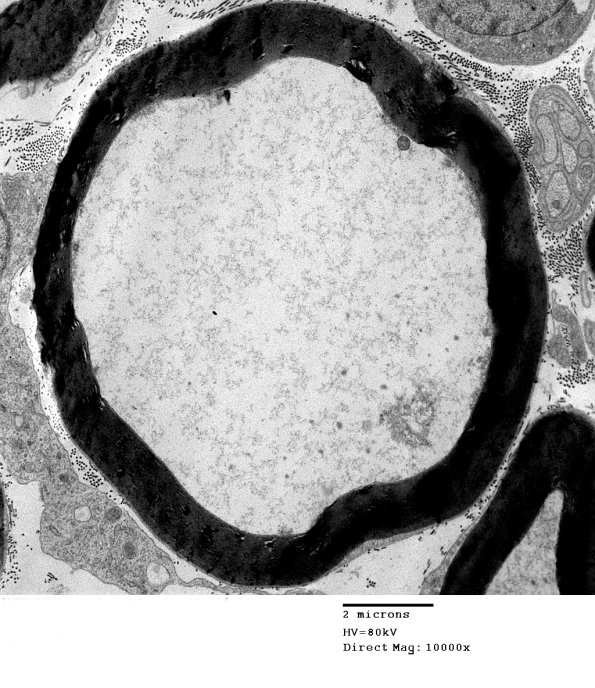

Washington University Experience | PERIPHERAL NEUROPATHY | 4 AXONAL DEGENERATION | 3 Electron Microscopy | 1F2 AMPK KO Mouse Degen Axons (Case 6) EM 011.jpg

Transgenic AMPK knockout mice show similar ultrastructural dissolution of the axonal cytoskeleton.